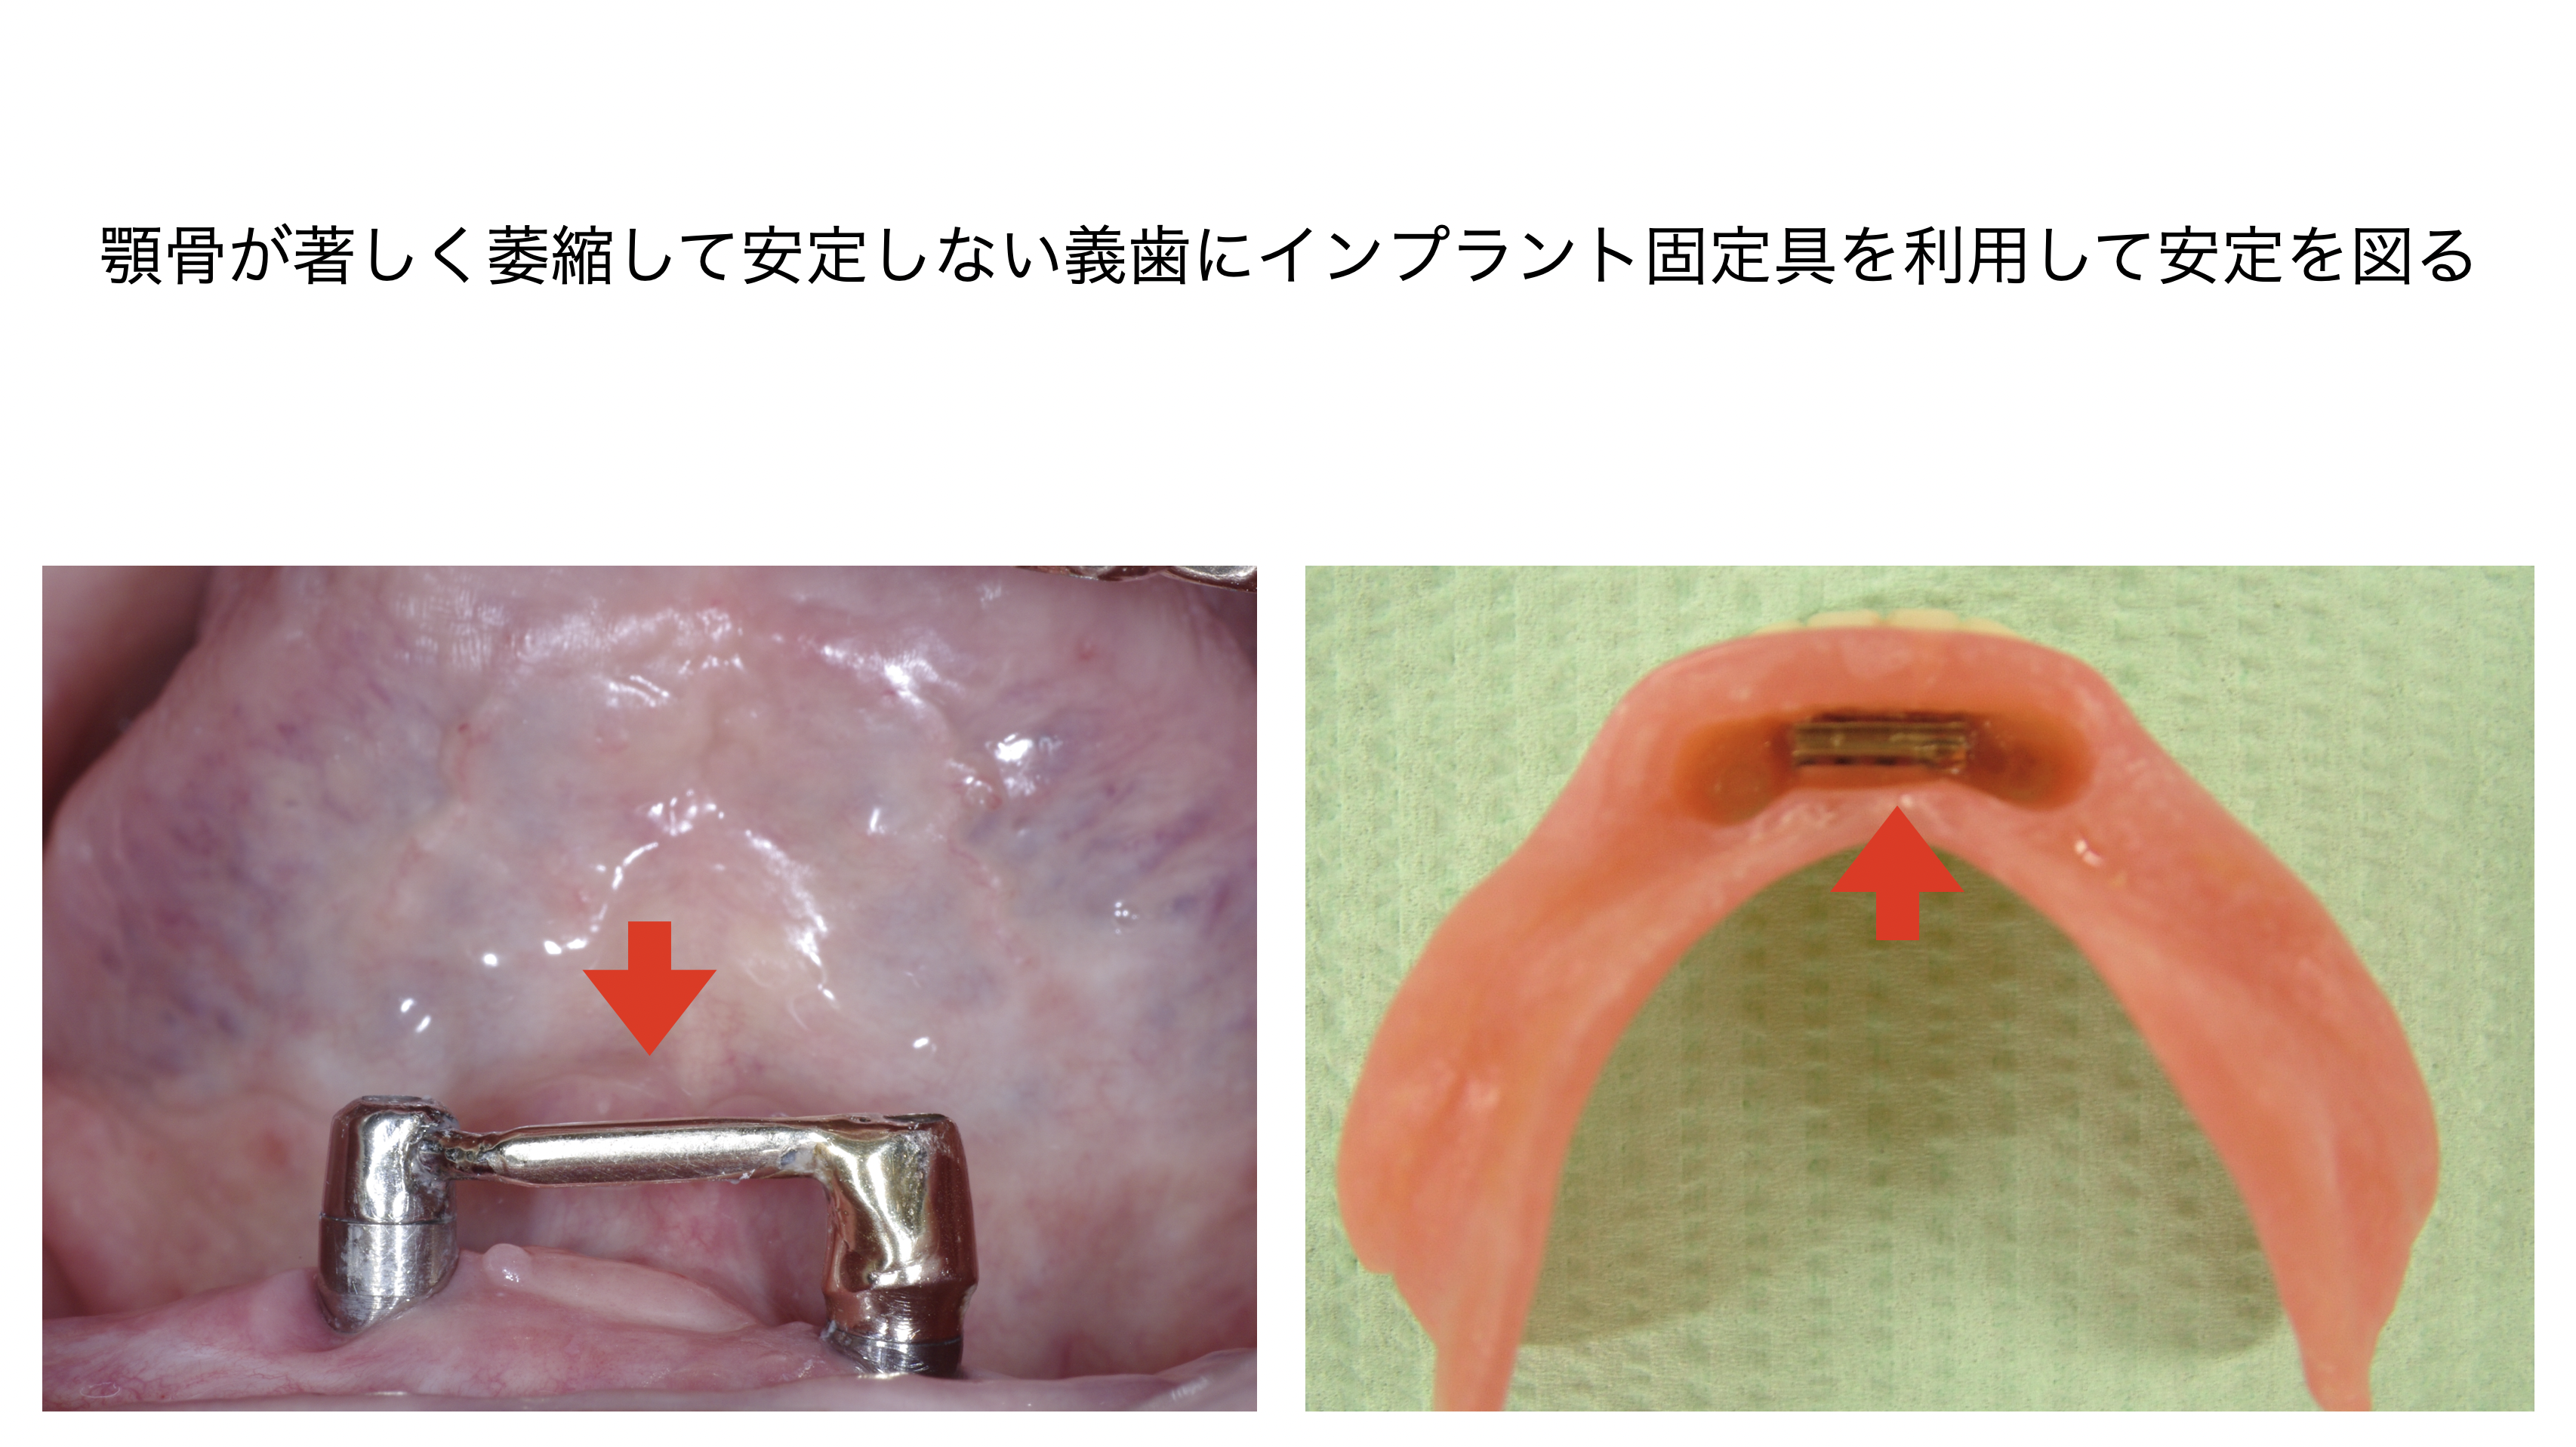

歯を抜くと廃用により、それまで歯を支えていた骨が急激に萎縮してしまいます。

萎縮した顎骨では、その後のインプラントや固定式ブリッジ、あるいは取り外し式義歯が困難になることもあります。美的な要件を満たさないことすらあります。

萎縮した顎骨では、その後のインプラントや固定式ブリッジ、あるいは取り外し式義歯が困難になることもあります。美的な要件を満たさないことすらあります。

補綴前外科処置は義歯をより快適に装着するための処置です。